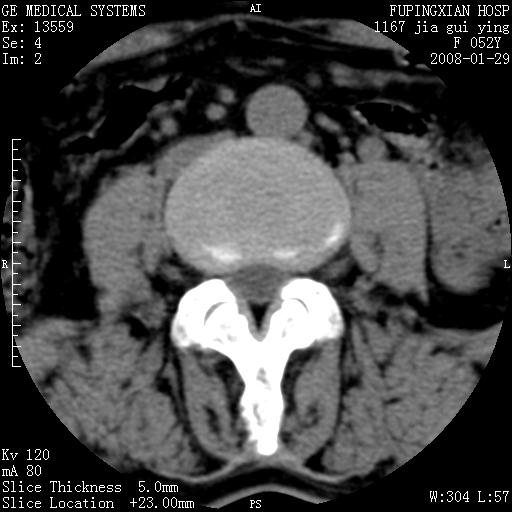

以下是引用dyqct在2008-1-29 21:49:00的发言:[br]考虑:1、腰4-5椎间盘突出(左椎间孔外侧型)。[br] 2、硬膜囊内钙化,多考虑蛛网膜炎所致粘连钙化,请询问病史病人以往做过碘油造影吗?

以下是引用liuyue在2008-1-30 4:32:00的发言:[br]1. 腰4-5椎间盘突出。[br]2. 硬膜囊内钙化,考虑a.蛛网膜炎所致粘连钙化;[br] b.硬膜囊内血管畸形.[br] c脊髓纵裂畸形.[br] 另:询问病史病人以往做过碘油造影吗?